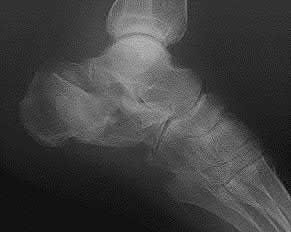

A 38-year-old male suffers the injury shown in Figure A. During operative fixation, free osteoarticular fragments are encountered and reconstruction of these pieces is attempted. Postoperatively, which of the following will have the most beneficial effect on the healing potential of the surviving chondrocytes within these reconstructed articular segments?

Figure A demonstrates a comminuted tibial plateau fracture with significant intra-articular involvement. Basic science evidence has demonstrated that post-operative gentle compressive loading may have a positive impact on articular cartilage healing; however, excessive shear loading may be detrimental.

Irrgang et al provide guidelines for rehabilitation following surgical management of articular cartilage lesions of the knee. They state that after articular cartilage repair, exercises to enhance muscle function must be done in a manner which minimizes shear loading of the joint surfaces in the area of the lesion. The authors also discuss the benefits of gentle compressive loading and motion of the joint, and its positive effects on chondrocyte nutrition.

Furthermore, they recommend a period of protected weight bearing as often being necessary, and that this should be followed by progressive loading of the joint.

Illustration A is a diagram showing the different layers of joint cartilage.